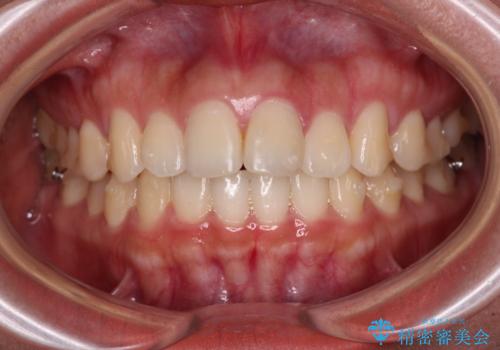

飛び出した上顎前歯 インビザラインで引っ込める

- 前歯の突出感を気にして来院された患者様です。

奥歯の咬み合わせは理想的な咬合に近く、インビザラインでも十分に対応できる歯列でした。

舌の突出癖を改善するためのトレーニングを行いつつ、上下歯列全体を後方に移動させ、更にはIPR(歯と歯の間を削る)によりスペースを獲得することで、口元の突出感を改善することとしました。